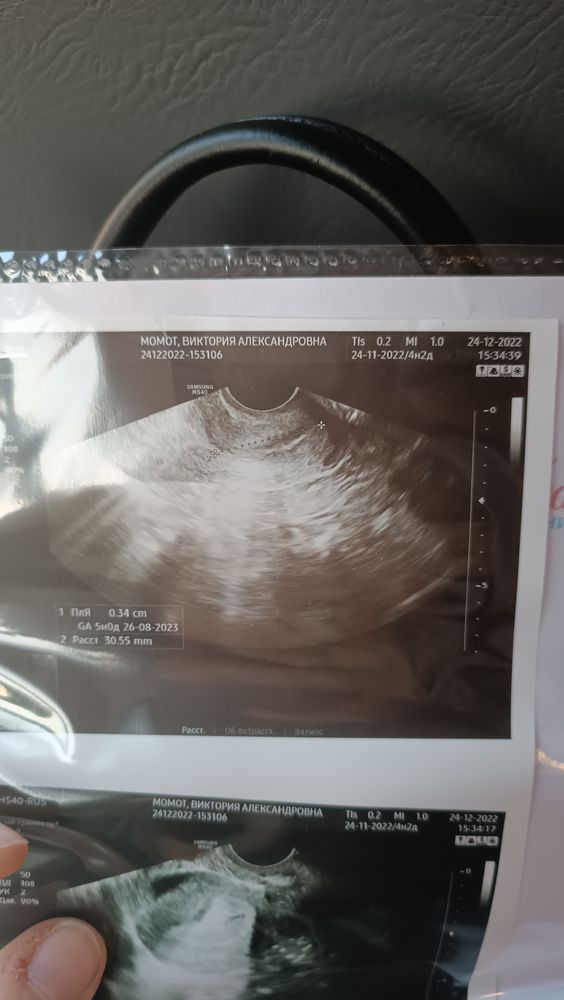

Мой срок беременности 4нед 2 дня, сегодня днём во время похода в туалет вышел маленький сгусток крови. Я сразу побежала на УЗИ, когда я сказала врачу что 3 дня назад хгч был всего лишь 32, она сказала мы ничего не увидим на УЗИ.

Она начала делать УЗИ, как вдруг мы увидели плодное яйцо, характерное для 5 недели, жёлтое тело есть, но эмбриона ещё не видно.

В интернете я читала что плодное яйцо видно с 1000 хгч, как оно могло у меня так быстро вырасти не понимаю.